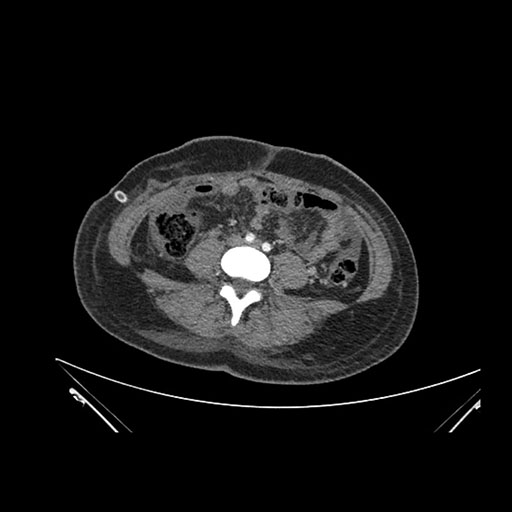

Imaging Analysis

Look through the patient's CT scan to identify any areas of concern for the necessary procedure.

Based on initial findings, which issue(s) would you be most concerned about?